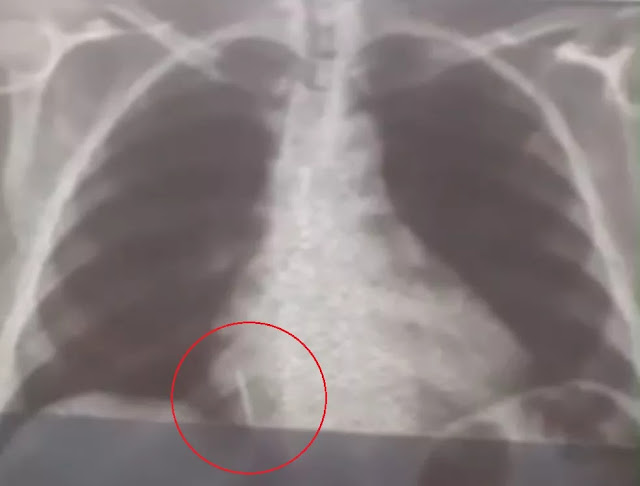

Iolanda Mariano de Melo Simplício está com o material alojado no pulmão deste então. O filho dela conta que a mãe sente muitas dores e já perdeu cerca de 10 quilos desde o ocorrido.

"A Secretaria Municipal de Saúde nos deu assistência para a realização dos exames. A gente foi para Natal inúmeras vezes com ela para fazer tomografia, raio-x, hemograma, risco cirúrgico, mas até agora nada. Já são quase 29 dias e praticamente não temos resposta. A gente quer uma solução, porque é um corpo estranho que está dentro do pulmão dela", conta Rohnhalyson Mariano.